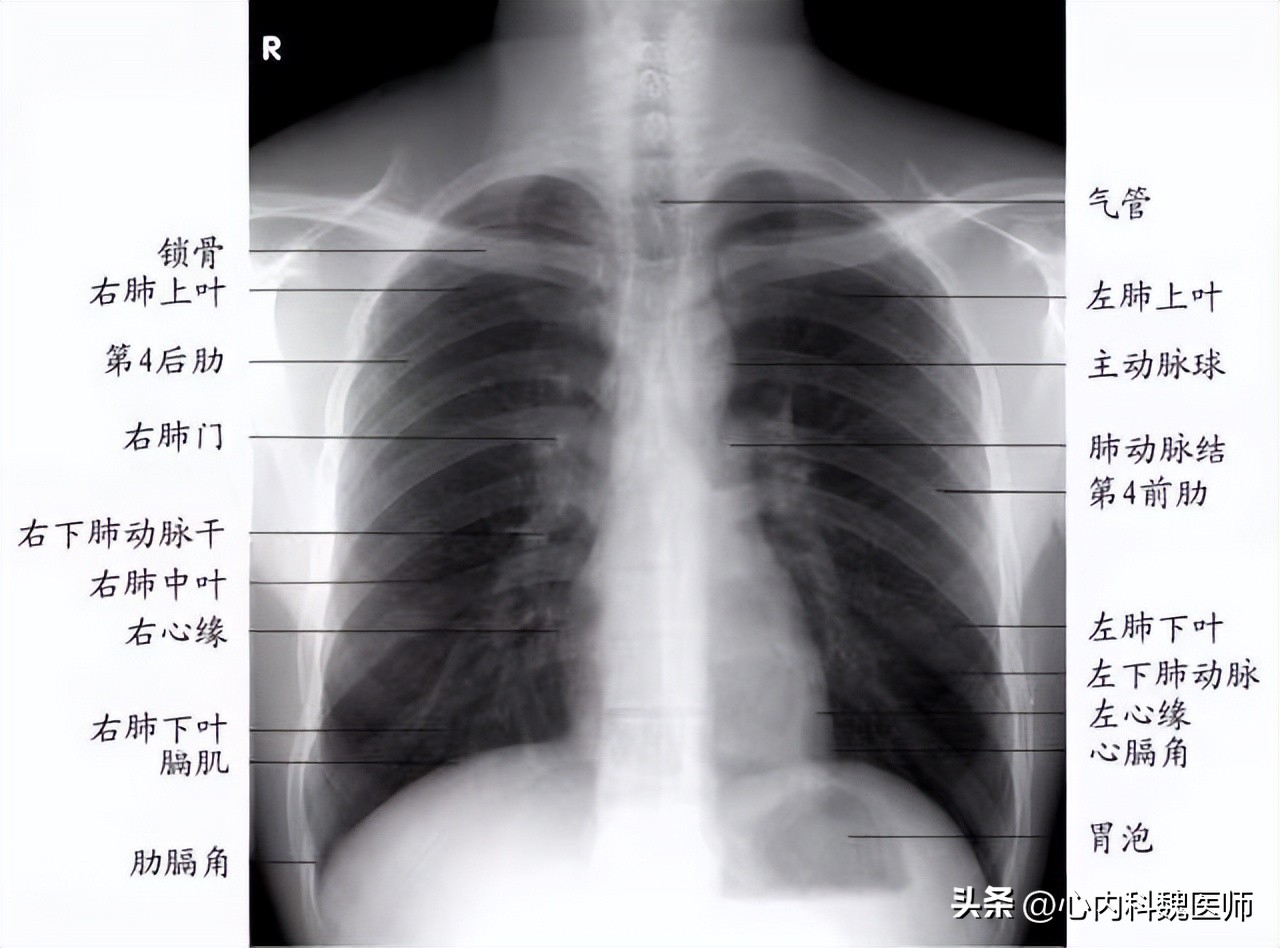

导致肺纹理增多的原因主要分为两种, 生理性因素和病理性因素 ,肺纹理增多作为病理性因素时不会单独出现;肺纹理是肺部出现的放射状态的状影,由肺部的肺门向外发出,总体呈树枝状影,由疾病原因或生理原因影响, 树枝状影会出现增多或中粗,这种现象统称为肺纹理增多 。导致肺纹理增多的原因主要有以下几种。

由疾病导致的肺纹理增多是病理性因素,主要分为淋巴性肺纹理增多,支气管性肺纹理增多以及血管性肺纹理增多。

肺部淋巴出现炎症或损伤影响肺纹理增多,肺纹理是肺间质的影像,肺间质组织包括肺部淋巴,因此肺部的淋巴影像是肺纹理形成的一部分, 肺部淋巴结发生炎症后会导致淋巴组织肿大,最终导致淋巴影像增多,由此发生淋巴性肺纹理增多。影像表现表现为两肺多细小网状阴影,出现这一特点及时检查肺部淋巴疾病。

支气管性肺纹理增多主要是由支气管疾病导致的,健康状态下的支气管肺纹理表现为粗细均匀的树状,受支气管炎症或支气管扩张影响,部分支气管会出现增多增粗现象。

支气管炎症会使支气管组织出现损伤,炎症物质也会附着在支气管组织上,因此支气管的影像学检查会受到影响,肺纹理影像检查中包括支气管影像,因此发生支气管疾病时肺纹理会受到影响,导致患者发生支气管性肺纹理增多。支气管扩张会影响肺纹理影像检查增多增粗, 发生支气管性肺纹理增多表现为肺纹理粗细不均匀,出现蜂窝状细小纹理 。

肺纹理反映肺间质影像,肺间质包括肺部血管,因此出现血管性肺纹理增多时常表现为肺纹理增粗,肺纹理多由肺门发出,按照肺部血管走向,出现这一特点可以确诊患者发生了血管性肺纹理增多, 出现血管性肺纹理增多且伴随心脏增大症状时可确诊为风心病或先心病等心脏疾病。